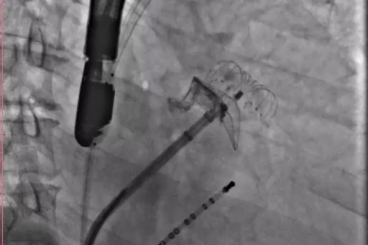

▲半发展固定伞,推送至锚定位锁死血栓

6.png        7.png

其中首场公开演示的左心耳血栓封堵病例拥有极高难度,患者术前TEE显示左心耳血栓形成伴机化,血栓位于心耳中段,近中端絮状物显著 。封堵机遇只有一次,选型和操作稍有失误,城市增长手术风险 。因而手术采取全麻,并装置了抗栓塞脑动脉;ぷ爸,以削减术中风险 。通过TEE疏导下丈量左心耳大幼以及确认左心耳血栓地位,李岳春教授凭借自身丰硕经验最终决定使用LAmbre 2632型号,选取推送式植入法将左心耳血栓牢牢锁死于远端,并且封堵器一次成型,封堵成效极佳,实现后取出脑;ぷ爸,均未见血栓,顺利实现了此台高难度的手术,获得了学员们的一致认可 。